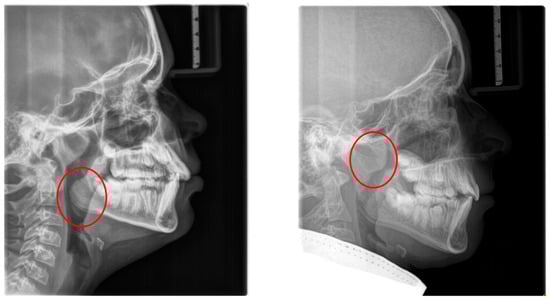

The consequences of these anatomical alterations result in a reduced size of the bony nasopharynx and a hyperdivergent facial pattern, characterized by increased anterior facial height. A bimaxillary retrognathic pattern, more pronounced in the mandible than the maxilla, and a decreased facial depth further contribute to a narrowed posterior airway space [83]. Together, these structural changes significantly reduce upper airway volume, thereby predisposing affected individuals to OSA (Figure 3).

Lateral cephalometry allows for systematic assessment of craniofacial structures, including both hard and soft tissues. Furthermore, it enables the evaluation of the sagittal dimension of the posterior airway space (PAS) and can therefore serve as a screening tool [101,102]. This diagnostic tool is reproducible, affordable, easily accessible in an orthodontic office, involves minimal radiation exposure, and is non-invasive [2] (Figure 6). The cephalometric radiographs are taken in an upright and natural head position, where the eyes focus ahead with a horizontal visual axis parallel to the floor (Frankfort horizontal plane). The occlusion should be the habitual bite (not forced into maximum intercuspation) and the lips in gentle contact (not forcefully closed).

Nevertheless, it is essential to note that the soft tissues in the upper airway behave differently when a person is asleep, in a supine position, compared to an upright position [103,104,105,106]. Several studies attempted to establish a relation between airway dimensions and craniofacial structures in subjects with OSA through cephalometric assessment [107,108,109].

However, a comprehensive assessment of the airway is better achieved with cone-beam computed tomography (CBCT). This three-dimensional evaluation offers a detailed visualization of the airway and the surrounding structures [110]. Though no universally accepted airway volume threshold exists to predict OSA risk, patients with OSA generally have smaller airway volumes compared to their unaffected counterparts [111]. No radiographic methods have been reported to have high specificity and sensitivity, serving as actual risk-assessing tools for OSA [100]. Moreover, the challenges of studying a functional airway using static images are inherently limited [112].